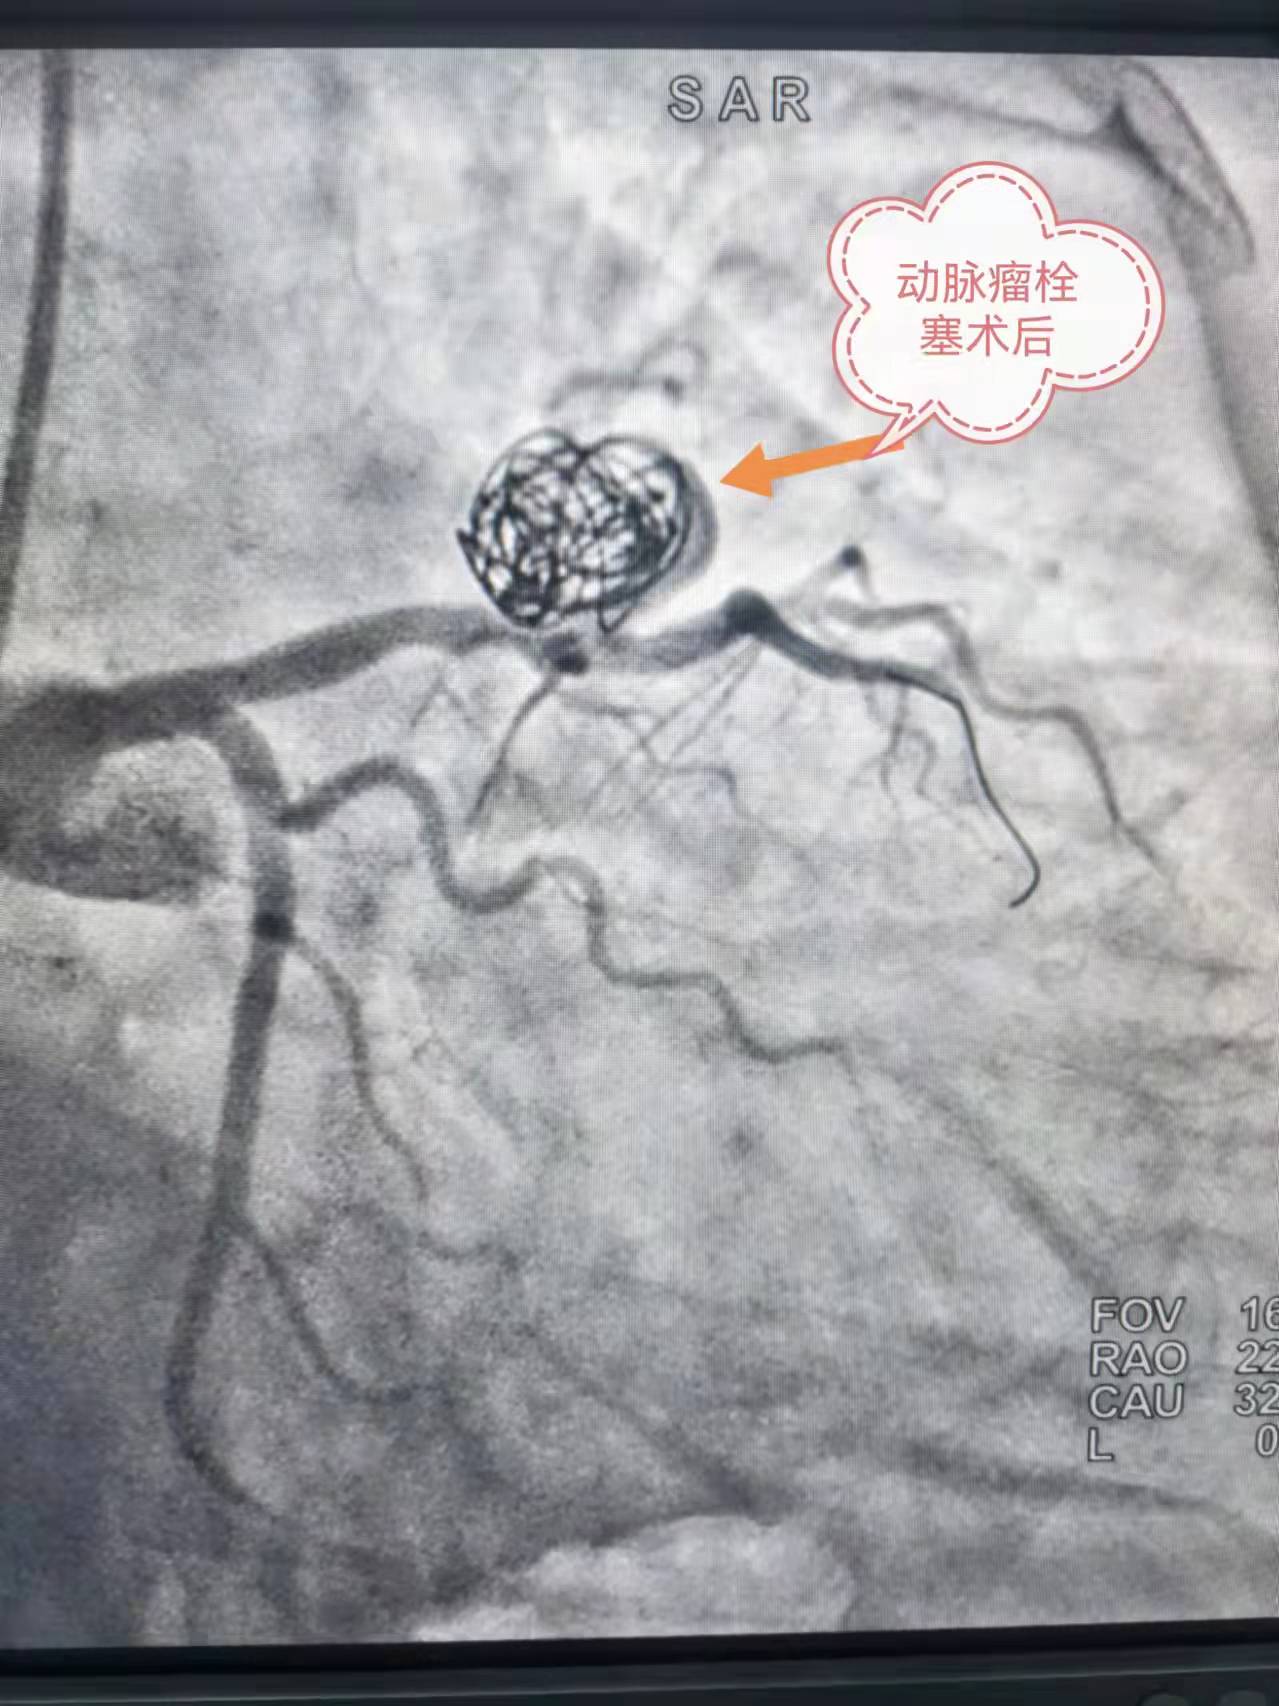

术后造影

12 月 25日,由胸痛中心黄权副主任医师、李军山主治医师以及介入血管外四科向斌主任组成的手术团队为患者实施经皮冠状动脉瘘栓塞术。首先经右桡动脉置入血管鞘,在DSA 血管造影系统下确定瘘口的大小及位置,术中沿微导管放置 4 个弹簧圈至血管瘤内释放,完美栓塞动脉瘤阻断肺动脉瘘。